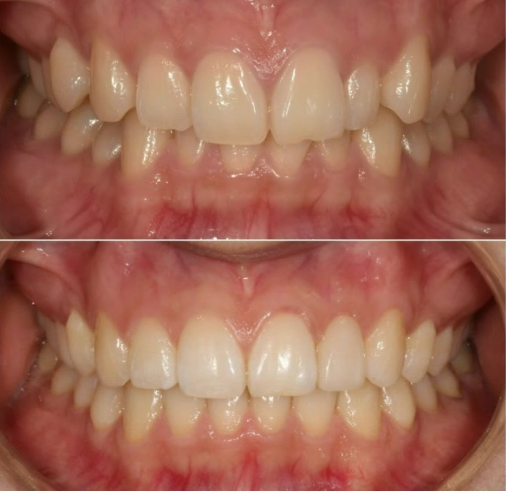

24.05

치료 마무리 단계의 사진입니다.

위 8개 아래 8개 앞니에만 장치를 붙여서 부분교정 진행중입니다.

왜소치에 라미네이트가 들어갈 공간 확보를 위해 스프링이 들어가있습니다.

7개월 후 교정이 마무리가 되었으며 왜소치 근처에 라미네이트가 들어갈 공간이 마련되어 있습니다.

이 공간을 이용해서 무삭제 라미네이트 라미네이트 젤라미까지 완료한 모습입니다.

반대쪽 치아와 같은 사이즈와 모양으로 왜소치가 회복이 되었습니다.

23.10~24.05

파란 화살표 왜소치는 정상크기로 치료가 되었습니다.

삐뚤한 앞니도 가지런해졌습니다.

교합이 떠 있던 작은어금니도 제자리를 찾았습니다.

앞니가 깊게 물리는 과개교합도 어느정도 해결이 되었습니다.

중심선 개선도 눈에 띕니다.

앞니 교정으로 이 많은 것들이 좋아졌습니다.

미소는 자연스럽게 개선이 됩니다.